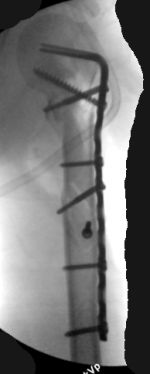

I just did this attached case, using 90 degrees angled blade plate, and this would be my preference in all similar cases.